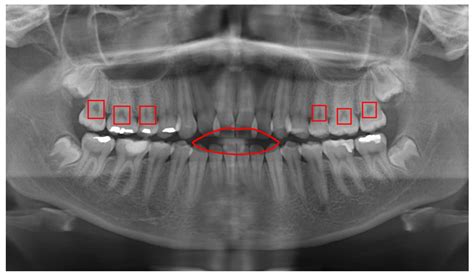

Sometimes, despite your best efforts, decay can still occur. Professional intervention is essential because decay does not heal itself. A dentist can use digital X-rays to detect interproximal decay—cavities forming between teeth that are impossible to see with the naked eye. When addressing tooth decay front teeth, dentists often prioritize aesthetic results by using tooth-colored composite resins that match your natural enamel, ensuring the repair is invisible to others.